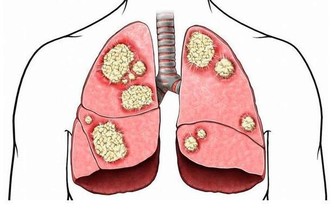

適合症狀:茶有明顯的防癌抗癌作用,堅持飲茶有防止腫瘤產生的積極功效